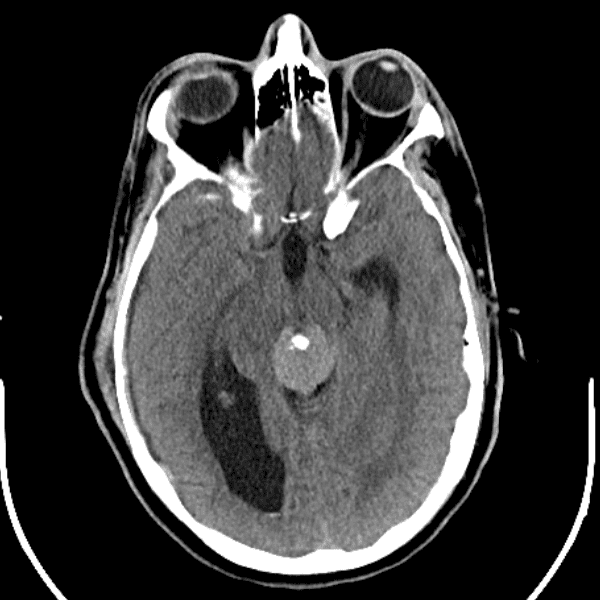

Classic Cases